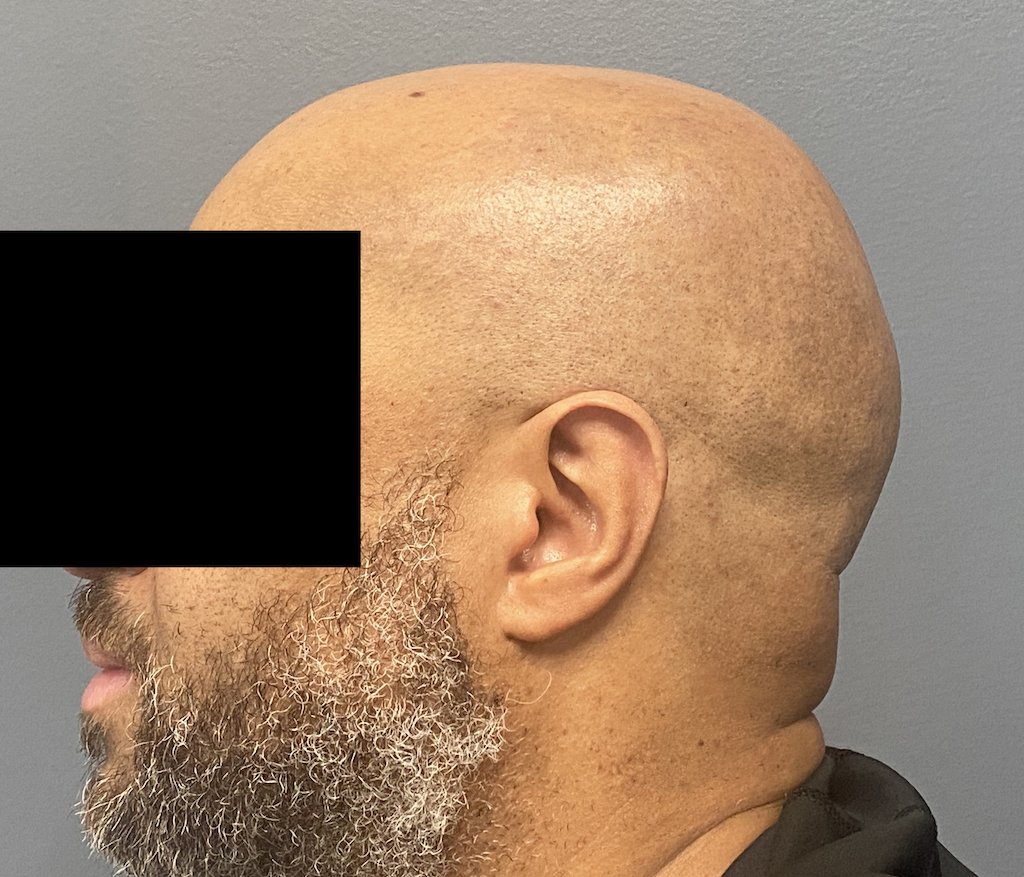

Young male seeking reduction of his convex sides of his head.

Head width reduction by posterior temporal muscle reduction through hidden postauricular incisions behind the ears.

Young male seeking reduction of his convex sides of his head.

Head width reduction by posterior temporal muscle reduction through hidden postauricular incisions behind the ears.